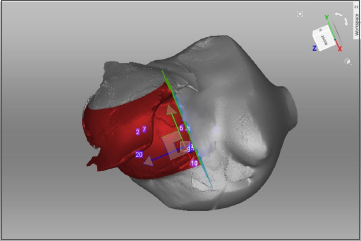

All patients underwent pre-operative volumetric analysis using both CT Angiography and 3D scanner. Post-operatively reconstructed breast volumes were measured using 3D scanner between 3-6 months. Breast volume on CT was measured by manually selecting the breast contour (Region of Interest, ROI) on each axial slice (Fig. 1). These ROIs were stacked to create a 3D reconstruction of the breast (Fig. 2). Hemiabdomen volume was measured on CTA from the anterior axillary line on the side of flap harvest, extending contralaterally up to the medial extent of the dominant perforator. This ROI corresponded to the anticipated DIEP flap territory based on perforator location and vascular dominance. Volume was then automatically calculated using Syringo.via software based on the cumulative ROI data(Fig. 3).

Figure 2. ROIs stacked to create a 3D reconstruction of the breast and the volume of the breast.

Figure 3. ROI corresponding to the anticipated DIEP flap territory based on perforator location and volume of hemiabdomen calculated.